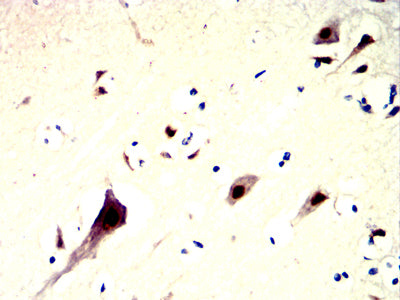

分类: 科研抗体货号: 32353别名: PARK8; RIPK7; ROCO2; AURA17; DARDARIN应用: IHC,FCM反应种属: Human